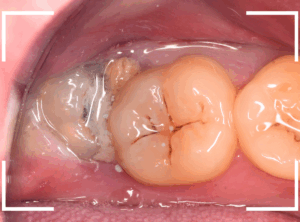

虫歯になった上のおやしらず

よくある、虫歯になっている上のおやしらずです。

歯の溝に沿って虫歯が進行しています。

虫歯の治療をしても、再発するリスクが高いです。

本格的に虫歯が進行する前に抜歯した方が良いでしょう。

抜歯も簡単に終わるケースが多いです。